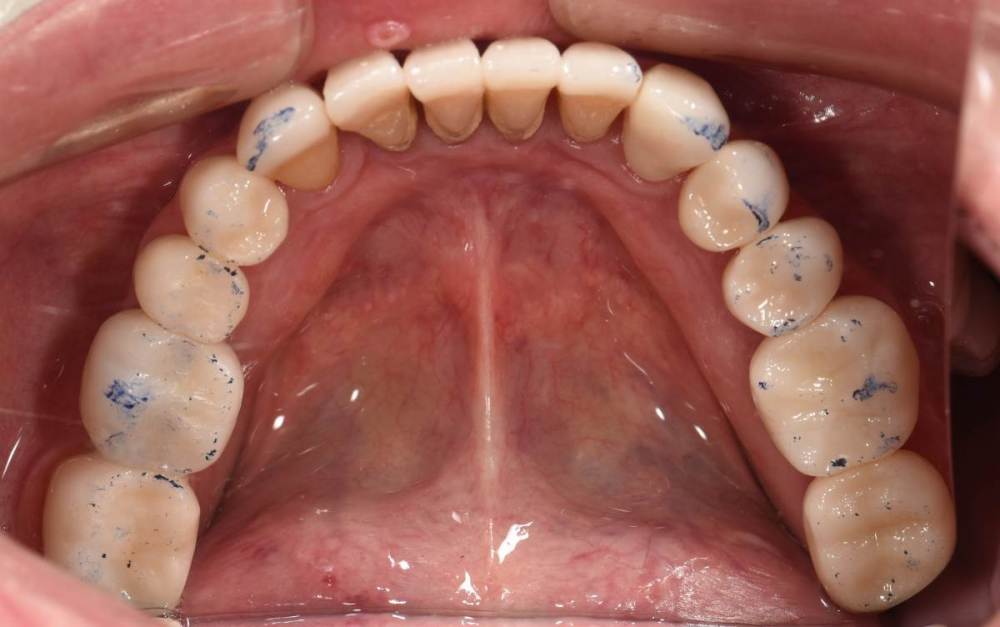

Финал работы:

DSC_3144.thumb.JPG.c9e60b8847f66dc01ba0e6e1113ab39b.JPGDSC_3145.thumb.JPG.1723748a079bc482f1a7e4534aff8f33.JPGDSC_3146.thumb.JPG.6dd4d0eb29dc3e6e92773c3c7892f692.JPGDSC_3147.thumb.JPG.e4f9cc2d841e3b7ff3aa73491ba9b4a3.JPGDSC_3148.thumb.JPG.0f174600adf2a49d65266a0ff665abfd.JPGDSC_3149.thumb.JPG.c9849be795d45b2573488d4545f3843f.JPGDSC_3150.thumb.JPG.6380366ecde7802fa32c6471b8b33883.JPGDSC_3153.thumb.JPG.1420d109d08ed1d6bd63447fe73eeed6.JPGDSC_3154.thumb.JPG.04b902149b3c0f9f2f1bcfa2e310c855.JPG

Фото спустя месяц после фиксации. Сначала нижняя челюсть, потом верхняя. Решение с передними нижними зубами - компромиссное. Все они витальные, имели 2-3 степень подвижности. После исправления положения нижней челюсти и установления правильных окклюзионных контактов - 1-2 степень подвижности. По поводу гигиены пытаемся.